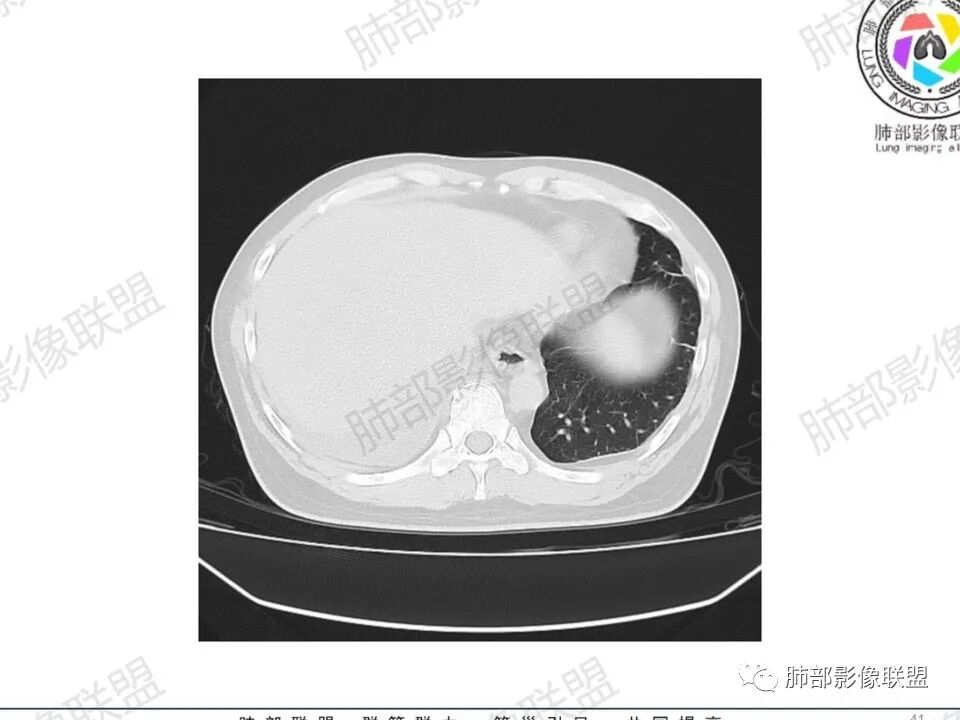

双肺多发结节,胸膜下为主,部分可见空洞。左肺上叶尖后段结节较大,分叶毛刺,周围可见长条索及小斑片影,内空洞比较光滑,内侧壁可见支气管通过。右肺下叶后基底段不张实变,后侧积液,右侧水平裂积液,右侧膈胸膜纵膈胸膜增厚积液,右侧侧胸膜肥厚,考虑1:一元金葡。2二元:金葡,左肺上叶结核。

男,45岁,左手指红肿疼痛两天,右侧胸壁疼痛伴发热12小时入院。患者急性起病,胸部CT示双肺多发结节,部分伴空洞,空洞壁较光滑,右侧胸腔积液,考虑感染性病变,金葡菌加SPE可能

@赵永兵 内蒙巴市临河妇幼影像科 支气管是从旁边经过,所以不是空洞,是胸膜下的脓毒栓。如果是结核空洞,应该与支气管相通(因为结核没有血播感染表现的时候,来源是气道,空洞应该与支气管相通),所以支气管从旁边经过,这病灶又在胸膜下,周围也没有干酪坏死。当然是SPE了。

中年男性,左手中指及胸壁疼痛伴发热来诊,影像见双肺多发结节,胸膜下分布为主,部分结节可见空洞,边缘模糊。左肺上叶尖后段结节较大。右肺下叶后基底段不张实变,右侧叶间裂及右侧胸腔积液,右侧侧胸膜肥厚。考虑金葡菌感染,血播SPE。

空洞内壁光滑,偏心厚壁空洞,张力高

胸水,部分包裹

支持血道来源感染性病变,金葡菌肺炎首选